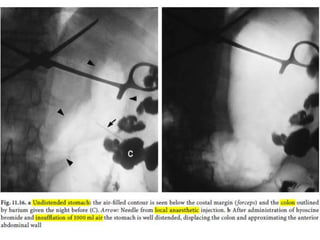

Gastric ulcer

• penetrate the stomach wall through the mucosa into the

submucosa and frequently the muscularis propria

• Among the most common gastrointestinal disorder and is amenable

to reliable radiographic detection.

• 95 % benign

– H. pylori (70 %)

– NSAIDs

– Alcohol abuse

• most prevalent in the distal stomach and along the lesser curvature.

• more common on the posterior wall of the stomach

• NSAID- and alcohol-related ulcers are most often seen on the

greater curvature of the antrum (direct toxic effect of the ingested

material)